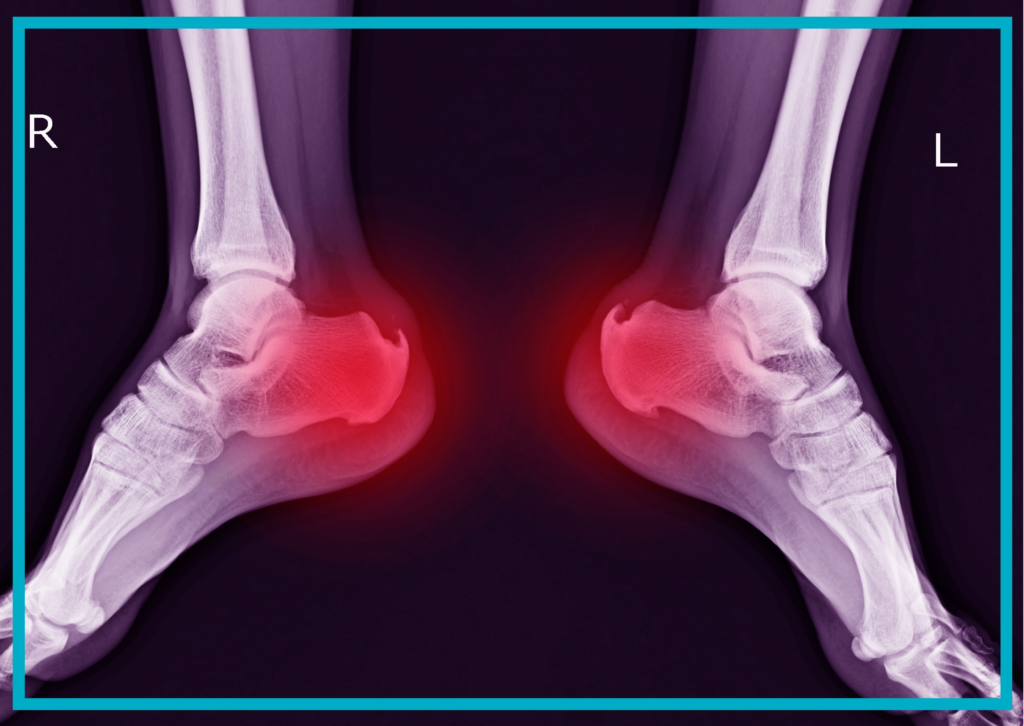

Terapia falą uderzeniową pomaga przede wszystkim w leczeniu schorzeń mięśni i stawów, skóry, chorób układu kostnego czy entezopatii. Stosuje się ją również, gdy występują stany pourazowe, w tym:

Od paru miesięcy odczuwałam silny ból pięty. Ból przeszkadzał mi w pracy. Nie pomogła zmiana obuwia, wkładki. Ortopeda powiedział, że to ostroga piętowa i polecił mi falę uderzeniową. Sam zabieg był trochę bolesny, ale już po drugim odczułam poprawę. Gorąco polecam.